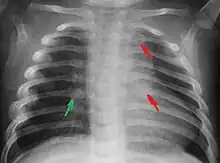

Fractures des côtes chez un enfant victime de maltraitance.

Fractures

Les enfants physiquement maltraités peuvent souffrir de fractures, particulièrement aux côtes[11].